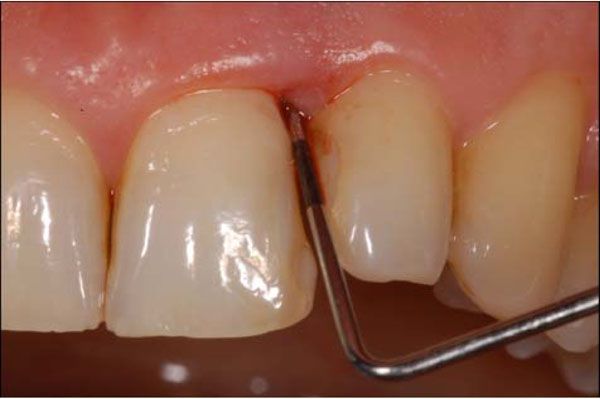

Examiner A using a standardized periodontal probe (CP11 Hu Friedy, Europe) detected: Plaque Index (PI) [9], Gingival Index (GI) [10], Probing Pocket Depth (PPD), and BOP (Fig. 2). The BOP was considered positive if bleeding occurred between 30 seconds after probing. Examiner B under endoscopic vision recorded the Endoscopic Biofilm Index (EBI) and the Endoscopic Calculus Index (ECI) at least 15 minutes later the preceding examination (Fig. 3) [11]. A time interval of 15 minutes was used in order to limit the possibility that the first exam, especially when bleeding was present, could affect the subsequent evaluation. The two endoscopic indices, reported on Table 1, have been recently purposed with the aim to distinguish different degrees and physical state of subgingival deposits.

Fig. (2).

Probing depth (PD) and bleeding on probing (BOP) recording.